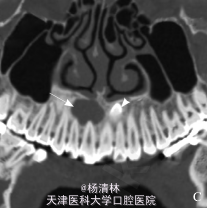

检查:12、11牙间的前庭沟区肿胀、压痛、触及囊性感;肿胀区相关牙未见龋坏、变色及异常松动,牙髓电活力检测试验反应正常。辅查:穿刺细胞学检查:穿刺得脓性囊液,涂片镜检见胆固醇结晶。 CT 示:左、右上中切牙与侧切牙之间根尖平面以上,骨组织内对称性分布的 2 枚多生牙;右侧见低密度囊性影,且多生牙包含其中。

诊断:上颌骨前部骨埋伏阻生多生牙并右侧含牙囊肿。处理:控制伴发的继发性感染后于局麻下行囊肿刮治及骨埋伏阻生牙拔除术,术后 7 d 治愈出院。

手术标本行常规石蜡包埋切片,病理表现为薄层复层鳞状上皮增生,钉突明显,纤维壁内见大量炎细胞浸润,病理诊断为含牙囊肿伴感染。 锥形束 CT 可以对颌骨病变,特别是多生牙的三维定位提供更全面、更准确的诊断依据,清晰地显示阻生牙的唇腭向、颊腭向、垂直向位置关系,并可以测量阻生牙与上颌窦、下颌神经管等重要解剖结构之间的距离,以确保手术安全,同时锥形束 CT 较普通 CT 具有辐射低、空间分辨率高的优点(病例来源于网络)